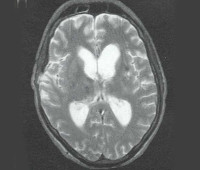

Диагноз «Диффузное повреждение аксонов» может быть надежно диагностирован по наличию патогномоничных макроскопических признаков при МРТ или КТ головного мозга. На КТ и МРТ головного мозга в остром периоде определяется отек мозга с уменьшением желудочков и субарахноидальных пространств; часто над лобными долями визуализируется накопление жидкости. Более сложным является диагноз ДАП легкой и средней степени тяжести, при котором макроскопические признаки обычно отсутствуют, отек мозга и кровоизлияние слабо выражены, а в некоторых случаях томографическая картина существенно не отличается от нормы. В такой ситуации они опираются на типичную томографическую динамику - регресс кровоизлияния и отек с тенденцией к расширению желудочков, последующей вентрикуломегалией и увеличением диффузной атрофии структур головного мозга.